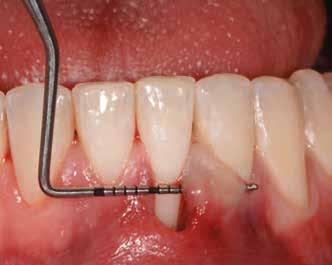

1. ábra: Műtét előtti fogászati panorámafelvétel, amelyen a hiányzó felső állcsont jobb első premolárisát és a szabad véggel rendelkező hidat láthatjuk. — 2. ábra: Az implantátum méreteinek megtervezése CBCT-vel. 3. ábra: Bukkális lágyrészdefektus. — 4. ábra: A biológiai szélesség értékelése a vertikális lágyszövetvastagság alapján. 5. ábra: Palatinális „tekercslebeny” – Palatal roll flap. — 6. ábra: Bredent medical copaSKY 4x10 implantátumbeültetés. 7. ábra: Szubkresztális implantátumbeültetés a várható biológiai szélességnek megfelelően.

8. ábra: Egyéni ínyformázó titánbázison, tulipán alakú emergenciaprofillal. — 9. a. ábra: A sebzárás okkluzális nézete.

(2. ábra). A lágyszövetek értékelése Seibert szerinti I. osztályú csontdefektust állapított meg (3. ábra), ezért a beavatkozáskor palatinális „tekercslebenyt” preparáltunk (palatal roll flap), és implantációt végeztünk, hogy kompenzálni tudjuk a bukkális lágyszövet-behúzódást. Megmértük a vertikális lágyszövetvastagságot, és úgy terveztük, hogy a szubkresztális implantátum beültetése összhangban legyen a biológiai szélesség kialakulásával a transzgingivális gyógyulási periódus alatt (4. ábra)